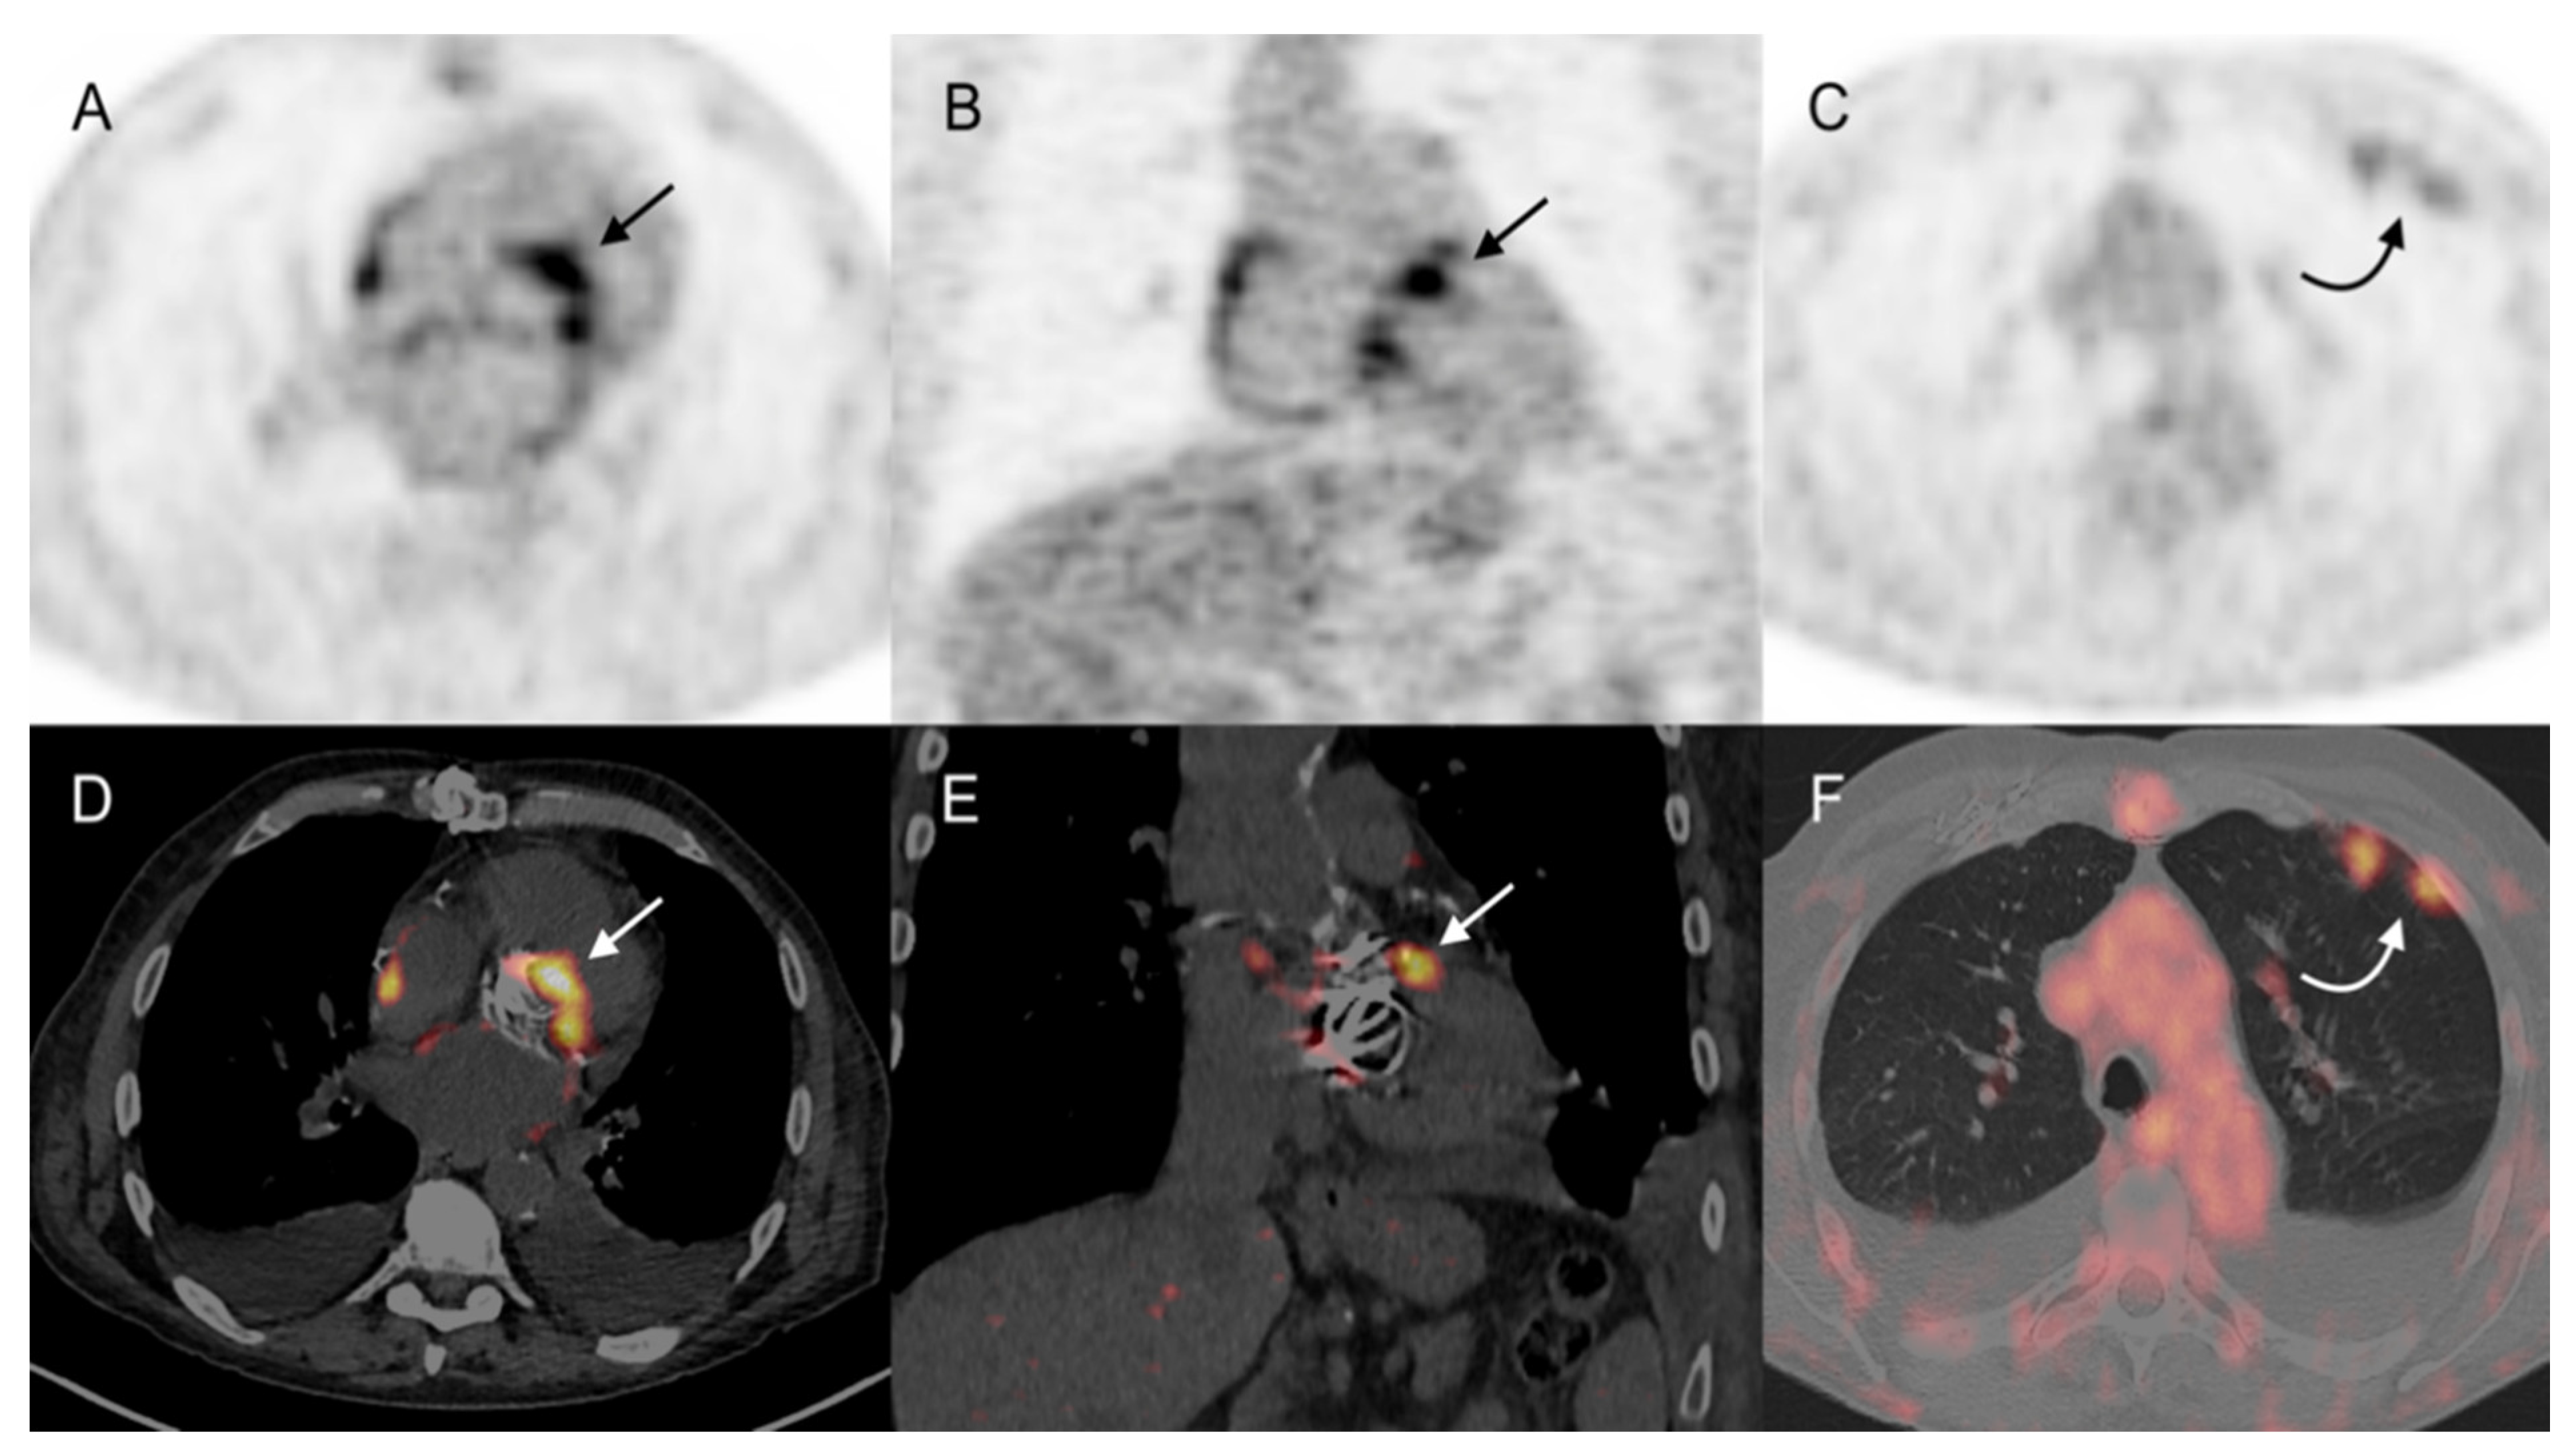

3.3.1. Cardiac Area Investigation

3.3.2. Extra-Cardiac Infection Assessment